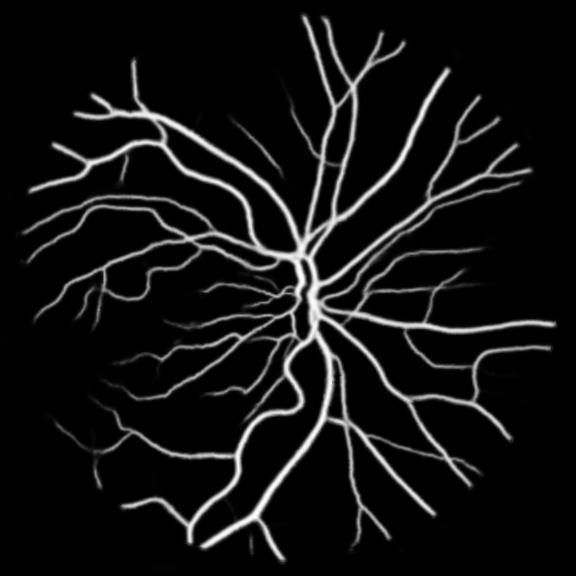

All three datasets are processed by subtracting the mean and normalizing according to the standard deviation. We use Adam optimizer, set the initial learning rate to 0.001 which is reduced by ten times if the training set loss does not drop during 10 consecutive epochs. We augment data using rotation, crop, flip, shift, change in contrast, brightness and hue. We set batch size to 4 for Skin Dataset and 32 for DRIVE and CHASE_DB1 whose patch size is relatively smaller. For each model we train 50 epochs and the result is shown in Table 1. Models with MixModule have better performance than those not and the best performance in each metric all comes from MixModule-based models. We also show some outputs of the networks in Figure 4.